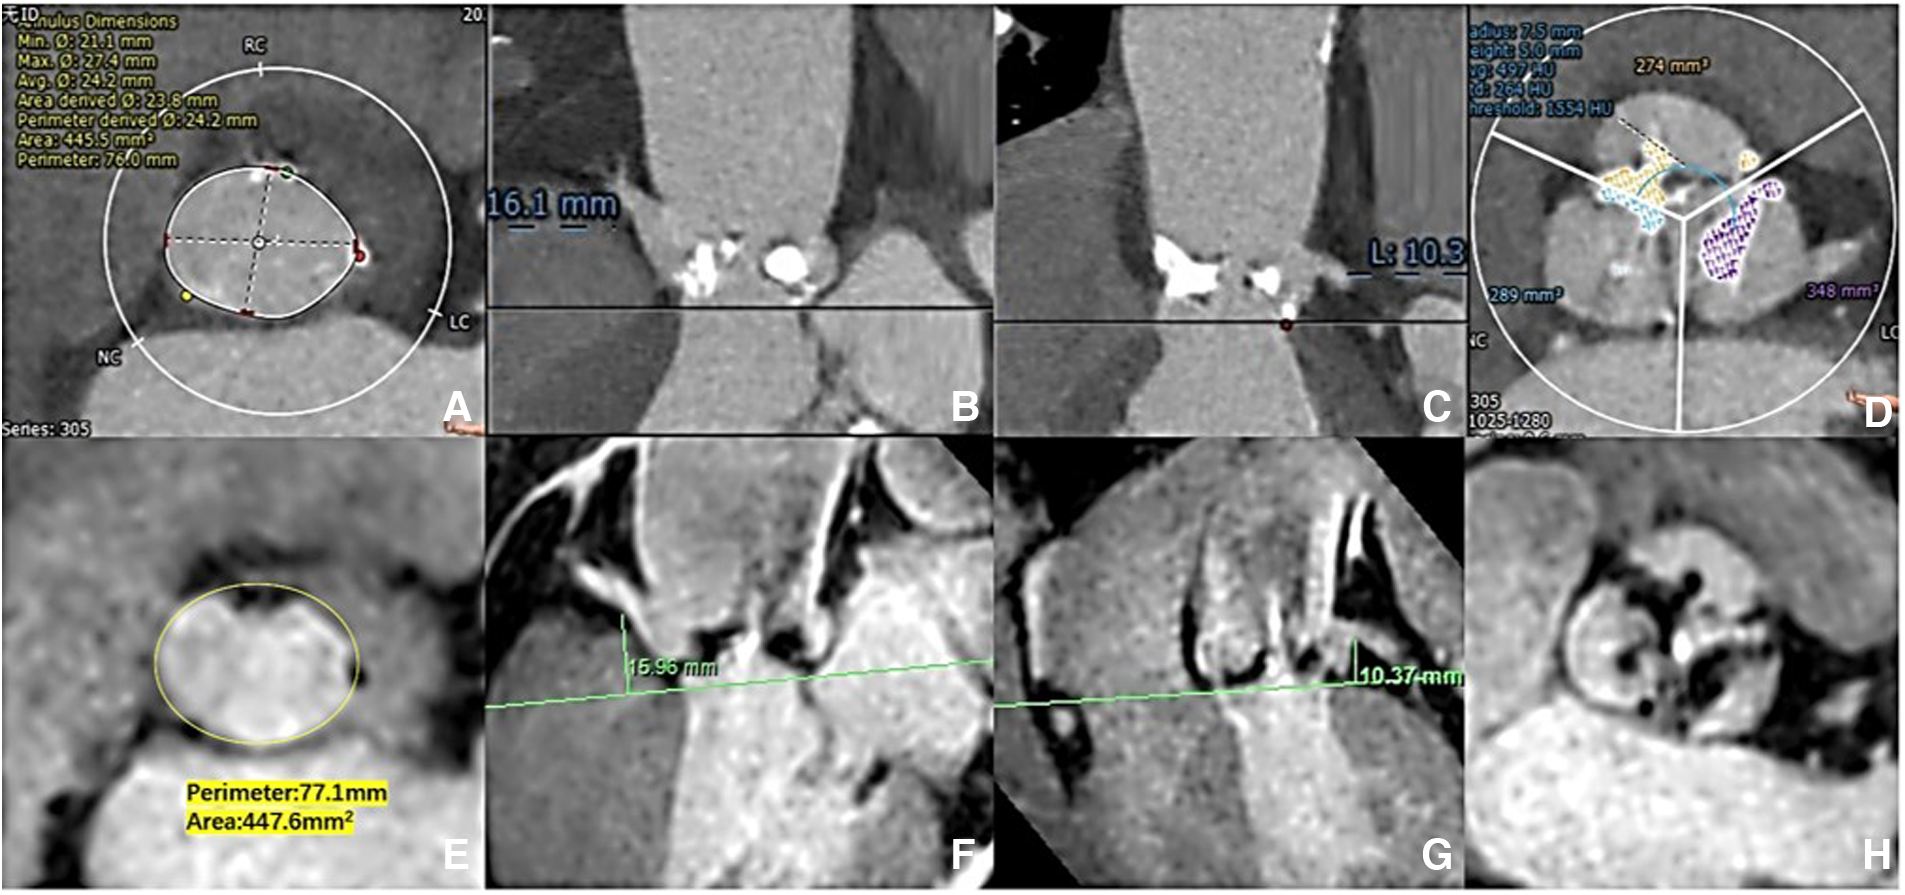

Aortic root measurement: CCTA vs. 3D whole-heart MRI. The aortic ring dimensions were assessed [(A) CCTA vs. (E) 3D whole-heart MRI]. The right/left coronary ostial heights were measured perpendicular to the annulus plane [(B,C) CCTA: vs. (F,G) 3D whole-heart MRI]. The extent of valve calcification was assessed [(D) CCTA vs. (H) 3D whole-heart MRI).

No significant differences were found in the perimeter, area, and average diameters of the annular ring and in coronary ostial heights between 3D whole-heart MRI and CCTA data. The diameters of the ascending thoracic aorta (37 ± 4.6 mm vs. 37.7 ± 5.2 mm, p = 0.085), descending thoracic aorta (24.3 ± 2.8 mm vs. 24.3 ± 2.8 mm, p = 0.832), abdominal aorta (20.9 ± 2.5 mm vs. 20.8 ± 2.5 mm, p = 0.602), bilateral common iliac arteries (right: 8.36 ± 1.44 mm vs. 8.42 ± 1.27 mm, p = 0.590; left: 8.61 ± 1.71 mm vs. 8.86 ± 1.46 mm, p = 0.050), and bilateral femoral arteries (right: 6.77 ± 1.06 mm vs. 6.87 ± 1.00 mm, p = 0.157; left: 6.75 ± 1.02 mm vs. 6.90 ± 0.80 mm, p = 0.142) showed no significant differences between REACT and ACTA data. Excellent agreement was found in aortic root dimensions and aorta and iliofemoral access route measurements for both modalities (Tables 2,3, Figures 2–4).

Aortic root anatomy: As previously described (5), the aortic annulus (area, perimeter, and diameter) at the hinge point plane, left ventricular outflow tract (LVOT), and the coronary ostium heights were measured by CCTA and 3D whole-heart MRI.